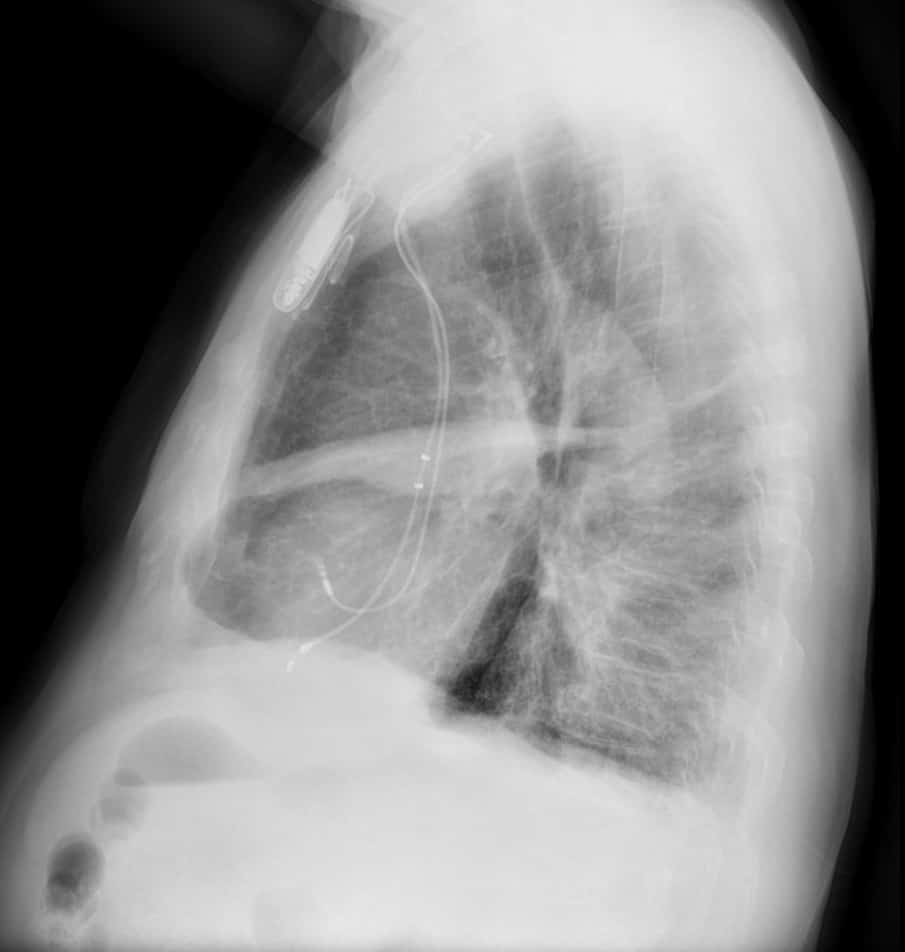

Tràn dịch màng phổi

Tràn dịch màng phổi - Ảnh 2

Tràn dịch màng phổi - Ảnh 3

» Thông tin: Nam giới – 46 tuổi.

» Lâm sàng: Ho + tức ngực.

# Tràn dịch rãnh liên thùy phụ phổi phải.